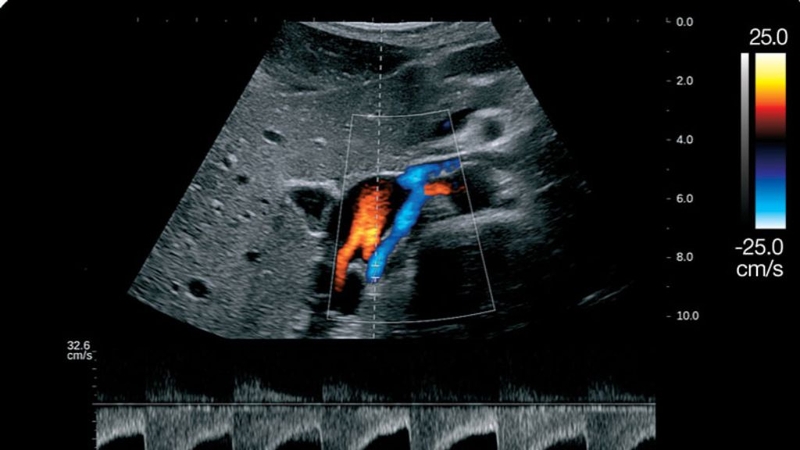

Đây là kỹ thuật siêu âm đường bụng dùng đầu dò 2D để ước lượng được trọng lượng của thai nhi. Bác sĩ sẽ đánh giá tình trạng phát triển của thai nhi xem bé có bình thường không, đánh giá trạng thái tim thai, bánh rau, nước ối cùng tầm soát các tổn thương khác.

Tương tự, phương pháp này sử dụng đầu dò 4D để dựng lên hình ảnh 3 chiều của em bé, chuyển động theo thời gian thực. Với siêu âm 4D, bác sĩ phải có chuyên môn cao, khéo léo, tỉ mỉ và quen thao tác với hệ thống máy móc hiện đại.